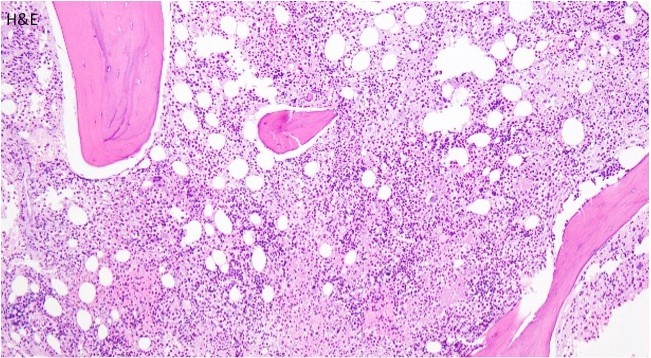

A biopsy of the bone marrow was performed.

Microscopic Findings

The bone core biopsy revealed a hypercellular marrow for the patient’s age with a pronounced lymphohistiocytic infiltrate involving 30-40% of the biopsied marrow space. Interspersed along the infiltrate were large, atypical lymphoid cells with pleomorphic nuclei and prominent nucleoli. The marrow aspirate smear reveals progressive trilineage hematopoiesis with scattered hemophagocytic histiocytes.